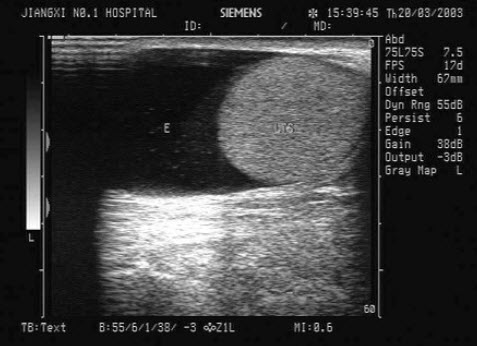

19、单项选择题

女性,39岁,胃癌术后。妇科检查:两附件区触及包块。超声检查如图,最可能的诊断为()

A.囊腺癌

B.囊腺瘤

C.黄体囊肿

D.转移性卵巢癌

E.无性细胞瘤